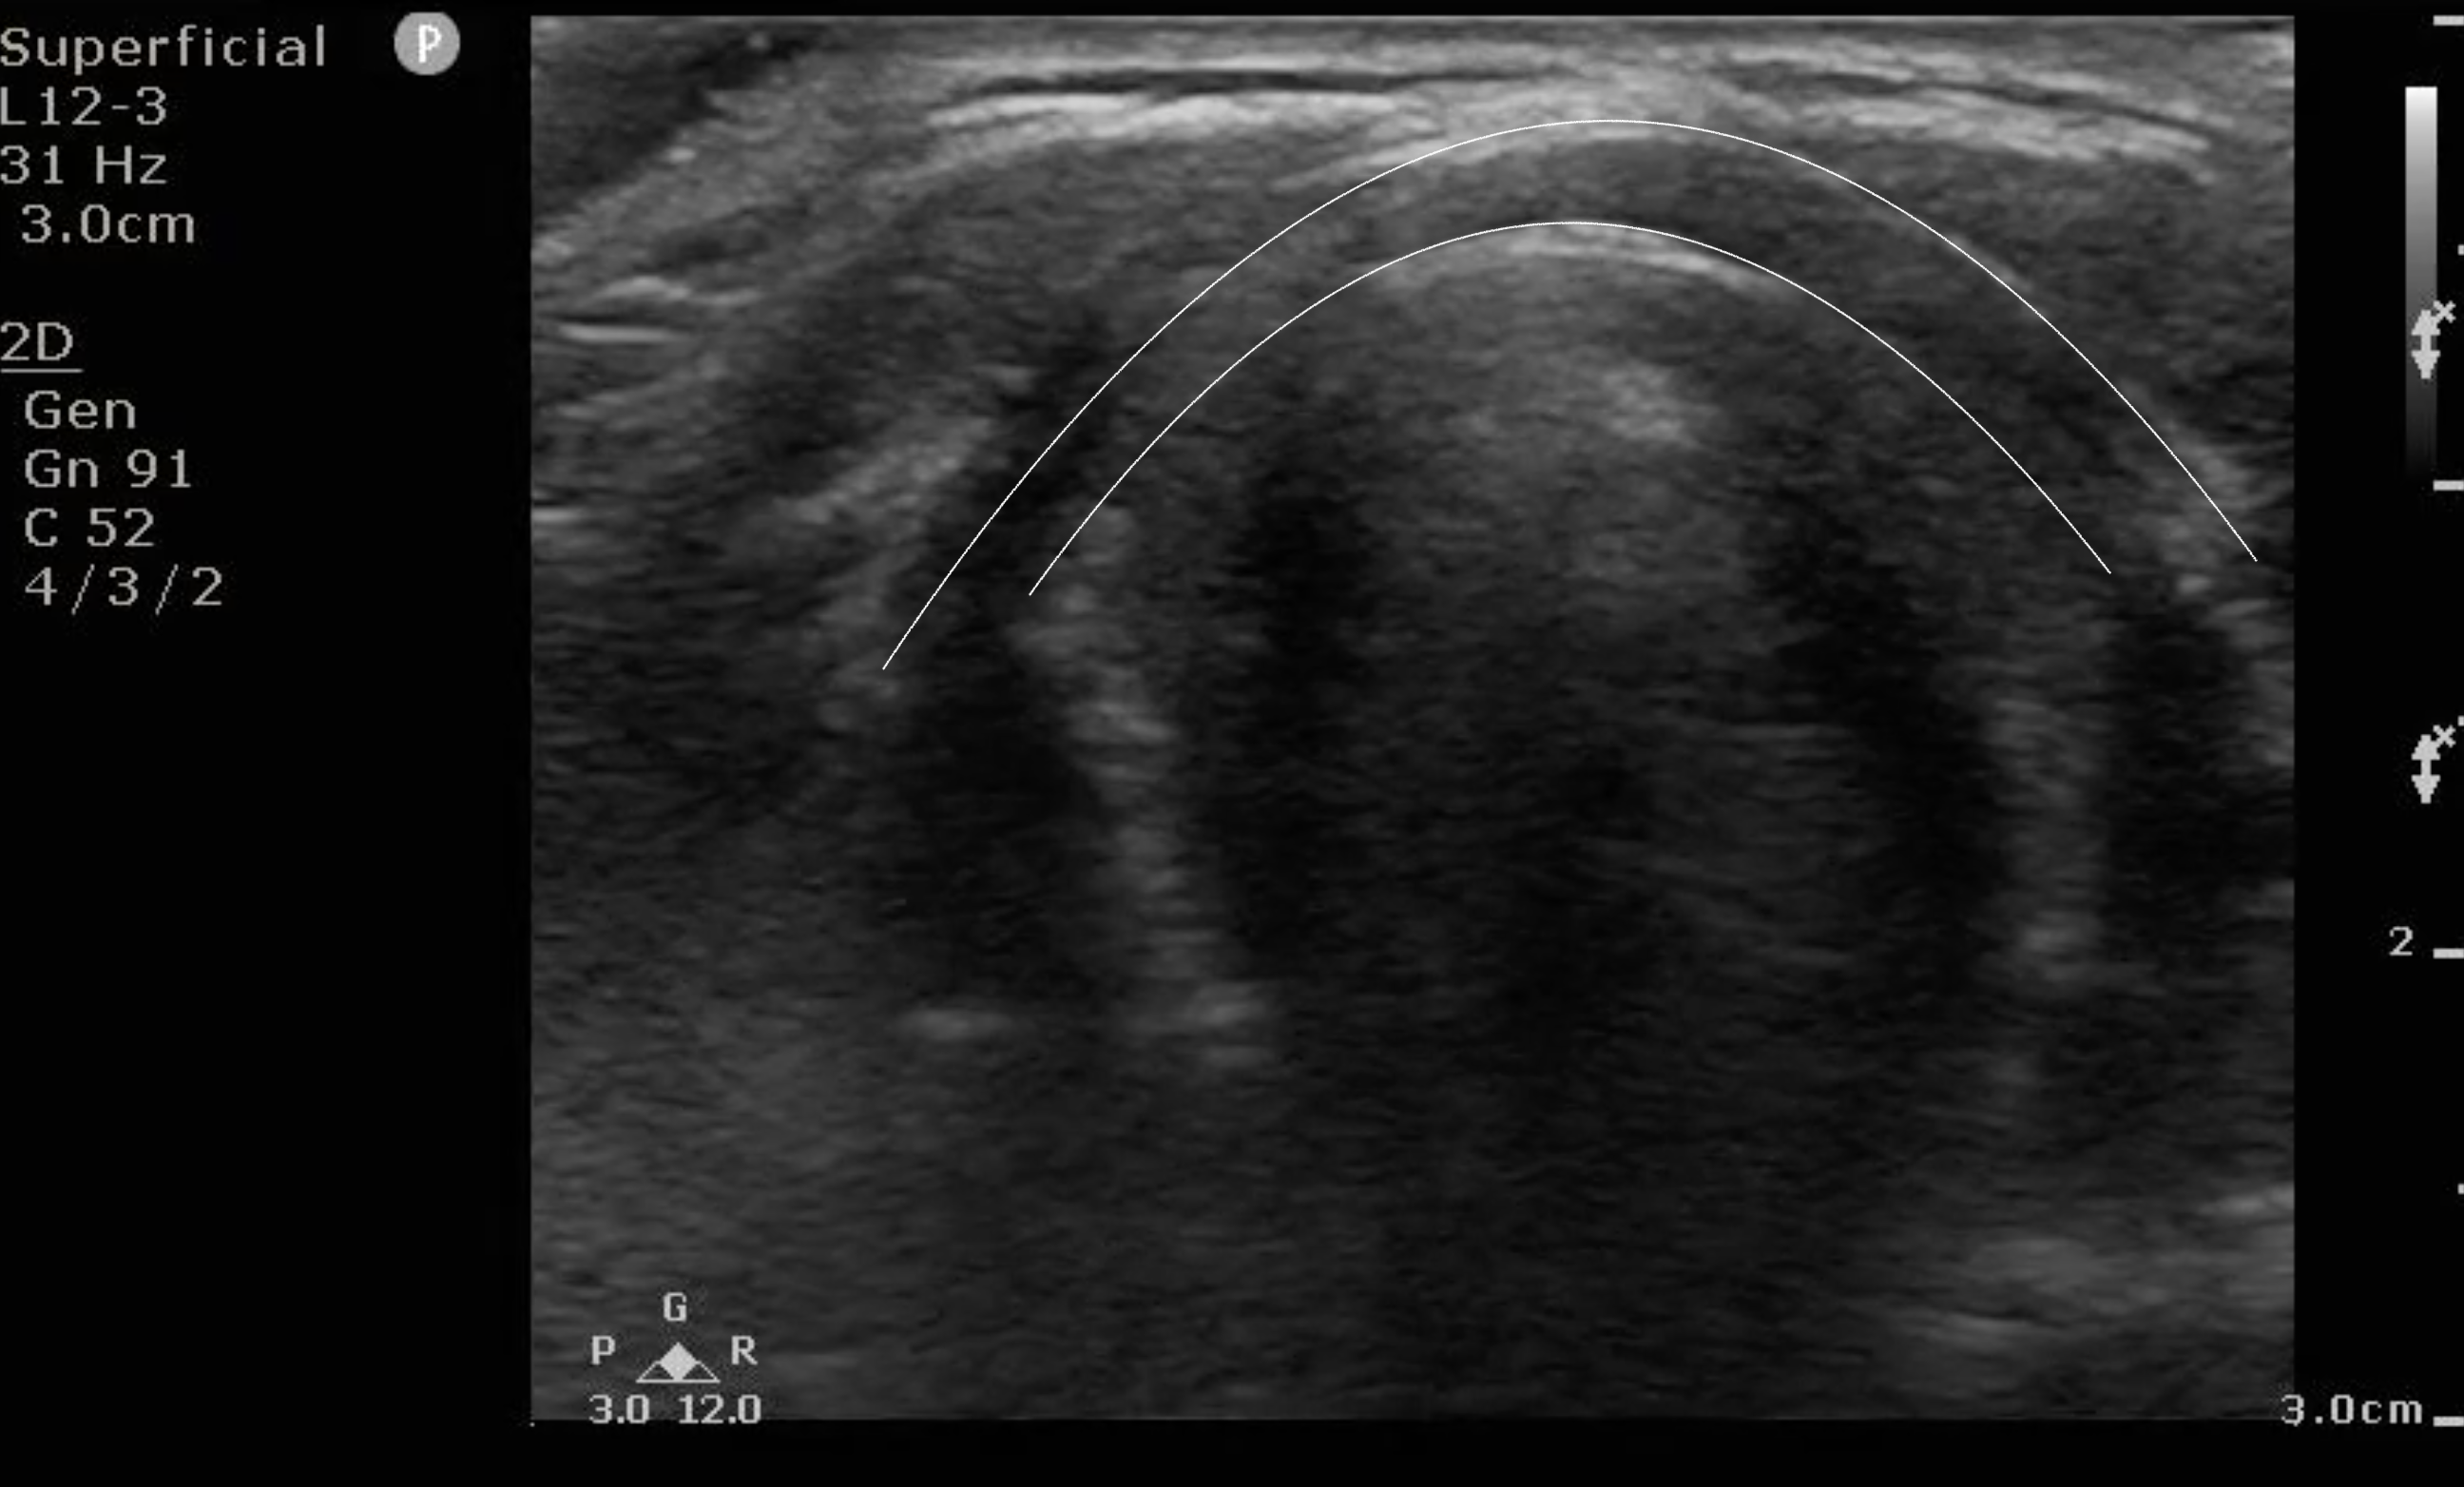

- Figure 2a and b. Step 2: Changing the angle of the probe to approximately 75° to the bed, you will see a dome-shaped hyoid bone with a hyperechoic edge and posterior acoustic shadowing, obscuring structures in the far-field.

- Figure 3a and b. Step 3: Sliding down the neck ever so slightly and keeping the angle of the probe approximately the same as finding the hyoid bone, you will see a hypoechoic band in the far field with two circular hypoechoic structures in the near field, forming a frog face-like image. The hypoechoic band is the epiglottis (E) and the two circular structures are strap muscles (SM) of the neck. Normal thickness of the epiglottis in adults is <3mm. Far field to the epiglottis are hyperechoic artifacts due to air; the bright linear line is the air-mucosal interface.